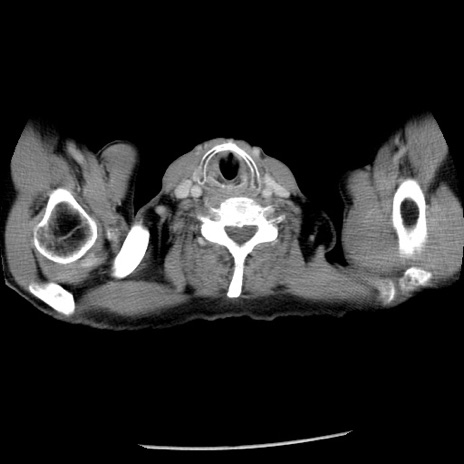

冠状断像

【症例】80歳代男性

【主訴】嘔吐

【現病歴】昨晩2回嘔吐あり、今朝になっても嘔吐あり。来院。

【既往歴】胃潰瘍

【身体所見】意識清明、BT 37.6℃、BP 166/95mmHg、HR 100bpm、SpO2 97%、腹部:平坦・軟、腸蠕動音聴取良好、圧痛なし。

【データ】WBC 21900、CRP 1.46